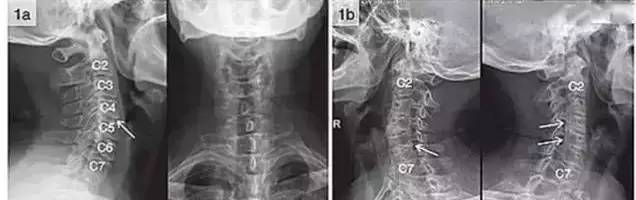

3. 双边征

可出现以下征象双边征:即某1或2个椎体后缘呈双边状,颈椎旋转5°左右

在正位片上出现棘突向一侧偏歪,标准侧位片上出现椎体双边征,双关节突

可出现以下征象双边征:即某1或2个椎体后缘呈双边状,颈椎旋转5